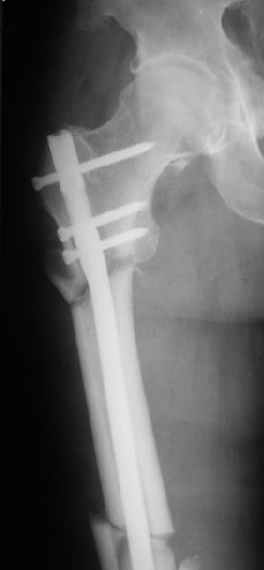

В частности, его возможности при фиксации переломов проксимального отдела бедра - в сравнении с другими, имеюшими лишь по одному статическому и динамическому отверстию и с кондуктором для введения 2 винтов.

Это было года 2,5 назад, мы тогда еще уточняли возможности шинирования с угловой стабильностью гвоздем с поперечным расположением винтов при переломах проксимального отдела бедра. Пациенту не пришлось приобретать намного более дорогой рекон или проксимальный гвоздь. В приложении еще несколько примеров применения того гвоздя при высоких переломах бедра, в том числе с более латеральной точкой входа. Гвоздь изгибаем для этого.